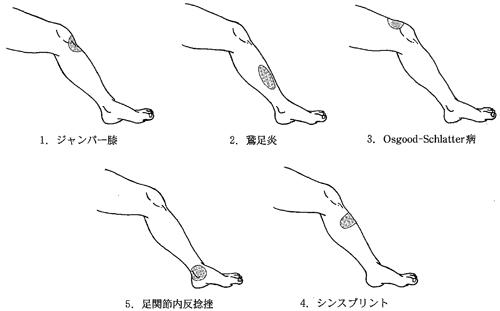

第45回 午後

スポーツ傷害に対する超音波照射部位で正しいのはどれか。

1

ジャンパー膝

2

鵞足炎

3

Osgood-Schlatter病

4

シンスプリント

5

足関節内反捻挫